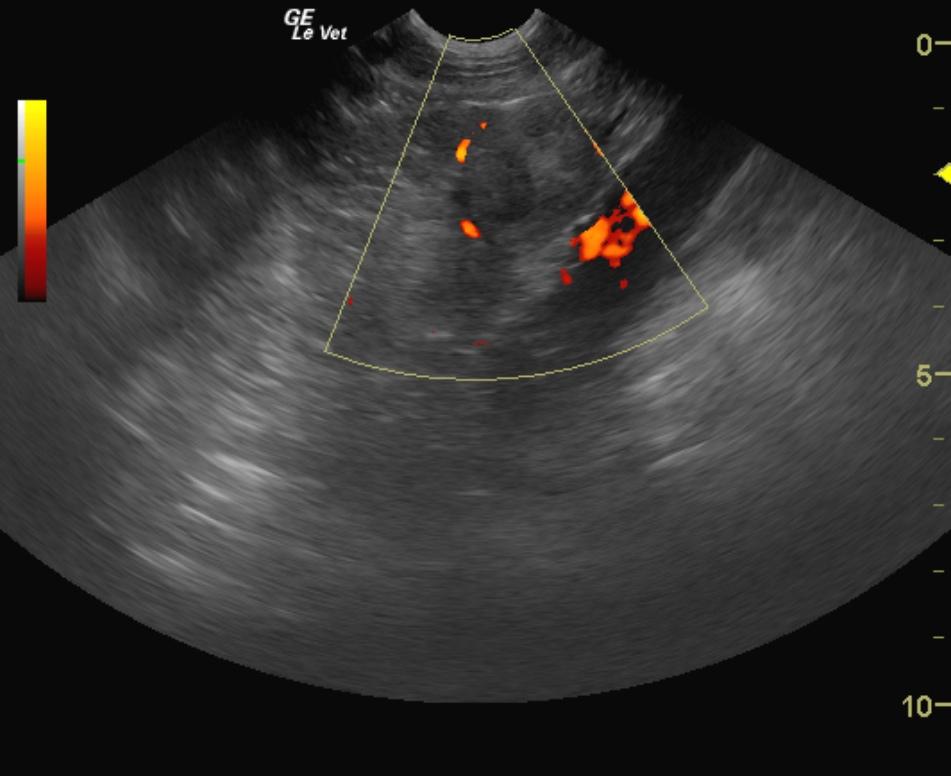

A 9 year old FS Labrador was presented for anorexia. Previous laboratory work had shown an inappropriate urine SG, 3+ proteinuria, microalbuminuria, azotemia, thrombocytosis, and negative 4Dx. The only significant abnormality on physical examination was dehydration. Baseline androstenedione and estradiol were elevated and ACTH stimulation revealed elevated cortisol, elevated estradiol, and elevated progesterone.